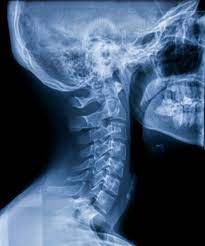

Imaging Overload How Many Tests Are Too Many Harvard Health

Imaging Overload How Many Tests Are Too Many Harvard Health from domf5oio6qrcr.cloudfront.net

You have to understand that the frequency of the radiation doesn't matter. This level of exposure will also increase your risk of a fatal cancer over the next few to several decades by about 5%. The lowest radiation exposure to cause radiation sickness is about 100 rem (1 sv). How are x rays harmful to the earth? What matters is the intensity of the radiation. More images for how many x rays are safe in a year » How many x rays are dangerous? (the atmosphere acts to absorb or deflect some of the cosmic radiation.

Those who don't have cavities can go a year or two between.